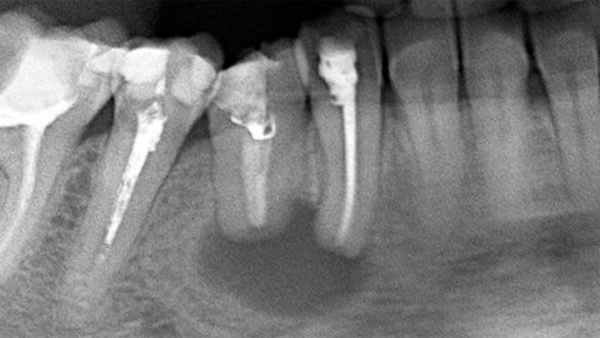

Для заполнения лунки нижнего моляра достаточно стандартной упаковки чипсов Остеоматрикса 0,5 см3, крошки Биоимплант ГАП 0,5 см3 и резорбируемой мембраны Биоматрикс 15х20мм. В качестве клинического примера приводим выдержки из истории болезни пациентки А., 23 лет. Диагноз: [K01.0] Ретенция зубов 48, 38 (рис. 5, 6) .

Рис. 5. Ортопантомограмма пациентки А., 23 г.

Заключительным этапом проводили контрольную рентгенограмму непосредственно после удаления зуба и через три месяца (рис. 16, 17) .

Рис. 16 а. Ортопантомограммы после удаления зуба 48.

Рис. 16 б. Ортопантомограммы после удаления зуба 38.

Послеоперационный период протекал без осложнений. На контрольной рентгенограмме можно проследить восполнение дефекта костной ткани в области дистальной поверхности нижних вторых моляров и отсутствие пародонтального кармана после удаления нижних третьих моляров.